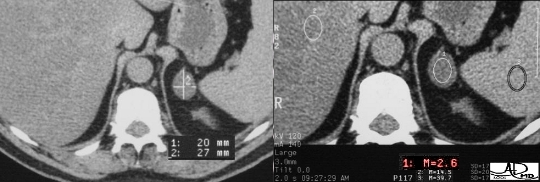

An “incidentaloma” is the most common adrenal tumor. It represents a small benign adenoma, (“oma” = tumor) of no functional significance, which is found incidentally, and hence its name. A nodule that is less than 3cm. with a density of less than 10 HU on CT, is diagnostic of the “incidentaloma”. The characteristic finding on MRI is a darkening in the “out of phase” T1 sequence of the tumor .

The nodule is oval, with smooth borders, measures less than 3cm., (left image) and has a density of 2.6 HU. (right image) It is a classical “incidentaloma” or benign adenoma. No further workup is needed. Courtesy of: Ashley Davidoff, M.D. |